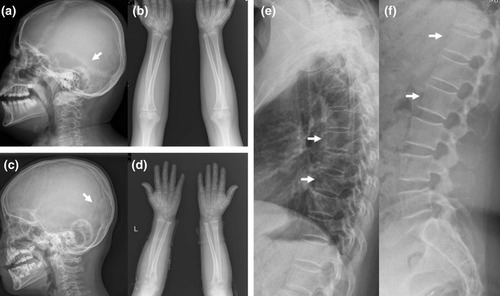

1994年にアメリカ・コネチカット州の男性が交通事故に遭っても、骨折ひとつしなかったので病院でX線撮影をしたところ、医師たちが驚愕することになりました。

同年代男性の「8倍」の密度を持っていたのです。

骨が異常に密すぎてX線がほとんど通らないほどでしたが、本人には痛み・障害・生活上の不便など一切なし。

この時点で医学界では前例がない“謎の超高密度骨”として話題に。

それから6年後、家族全員が同じように異常な骨密度を持つことがわかり、遺伝によって受け継がれた特異体質だったことが判明しました。